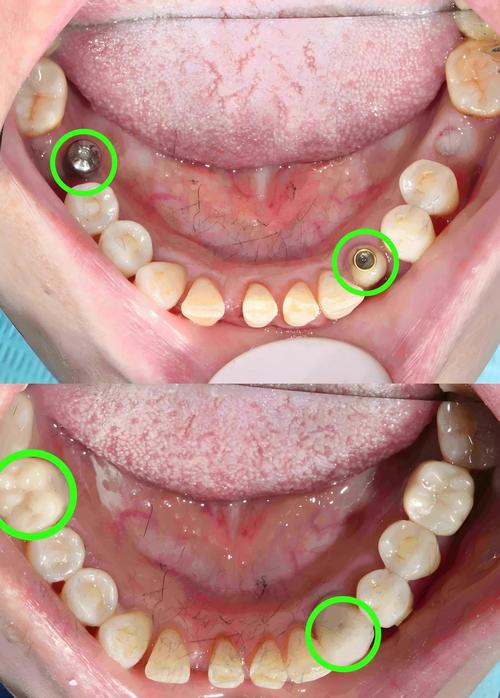

- 两颗种植牙支持三颗牙冠(种植桥):

- 方法: 在缺牙区的第一颗和第三颗牙的位置植入两颗种植体,然后在两颗种植体上制作一个三颗牙冠的桥体(中间一颗假牙“搭”在两颗种植体上)。

- 优点: 手术次数少(只需两次植入种植体),总费用相对较低,治疗时间可能稍短。

二期手术(如未同期愈合基台):

切开牙龈,安装愈合基台,塑造牙龈袖口形态(约2-4周)。

- 用数字化扫描或传统取模方式获取精确模型。

- 技工室根据模型制作个性化基台和全瓷牙冠。

- 试戴基台和牙冠,检查就位、咬合、接触点、美观效果。